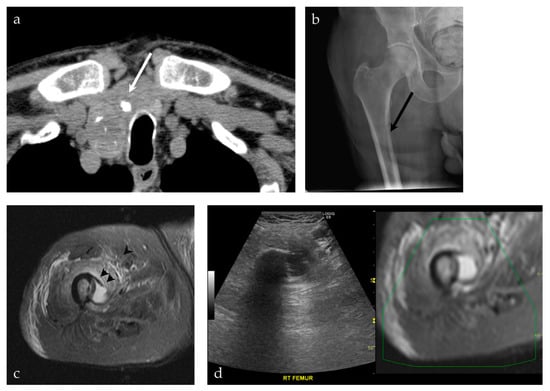

| 24/M | Right inferior pubic ramus | US-CT | Ewing sarcoma | Neoplastic, malignant |

| 93/M | Right femur | US-MRI | Metastatic disease, papillary thyroid carcinoma | Neoplastic, malignant |